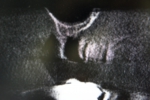

根管治療レッジ除去リカバリー症例

術前 ➡

術中

根の先に影(感染)が出てしまい根の治療を行わないといけないのですが以前他院にて処置を施した古い薬が入っています

画像を見ると手前の根にはしっかりと先まで薬が入っていません(1枚目の画像)

根のカーブに対応できず間違った方向へ削り込んでしまっています(赤矢印)

古い薬を除去しとあるテクニックを駆使し正しい根幹への道を見つけました(青矢印)

簡単にやっているように見えますがそのまま器具を入れては大きく間違った道に導かれてしまうなか、その脇から1mmにも満たない狭く曲がった孔を探しそちらへ導くのは至難の技ですが、マイクロスコープとCTを使いしっかりとした手法で行うとこのような症例にも対応できます